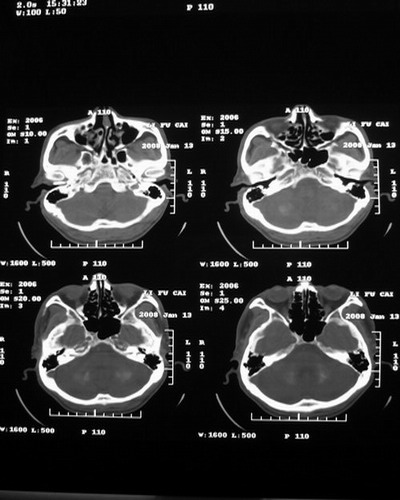

以下是引用随光逐影在2008-1-14 17:26:00的发言:[br]考虑为:甲状旁腺功能低下。需与fahr`s病相鉴别。建议:实验室检查。